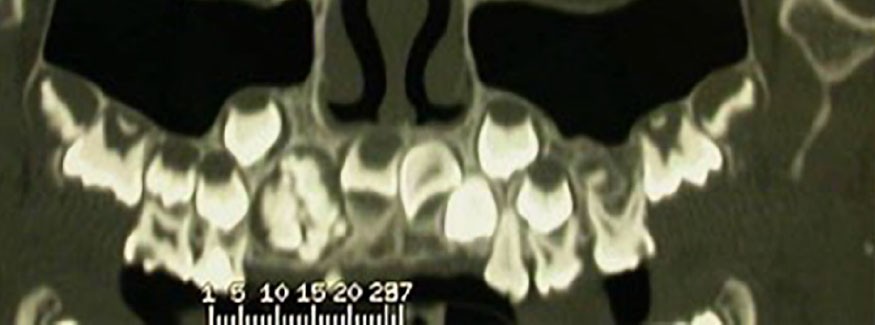

Les odontomes sont des tumeurs odontogéniques bénignes de type hamartomateux. Selon Broca, ils sont formés par une croissance excessive de l’ensemble des tissus dentaires compromettant parfois, lorsqu’ils se développent dans leurs trajets, l’éruption normale des dents.

– l’odontome composé, correspondant à une masse dont l’anatomie ressemble à une dent ou à un ensemble de petites dents rudimentaires assemblées en amas, le plus souvent dans la région antérieure du maxillaire ;

– l’odontome complexe, décrit comme une masse anarchique de matériaux dentaire, retrouvé plus fréquemment dans les régions molaires, prémolaires.